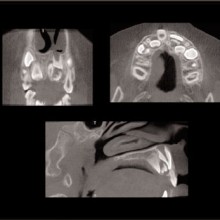

TEMPOROMANDIBULAR JOINT EVALUATION: It is not uncommon for individuals seeking dental treatment to have TMJ conditions that may alter the size, form, quality, and spatial relationships of the osseous joint components. When these conditions occur during development, they may alter the growth of the ipsilateral half of the mandible with compensations in the maxilla, tooth position, occlusion, and cranial base. Severe TMJ conditions may also alter the facial growth pattern. Skeletal and dental changes occur in the vertical, horizontal and transverse directions thus making them difficult to accurately characterize with conventional two-dimensional imaging, such as cephalometric, tomographic, and panoramic projections. CBCT creates the opportunity to visualize and quantify the local and regional effects associated with the TMJ abnormalities. CBCT allows, for the first time, to visualize the TMJs and at the same time, assess the maxillomandibular spatial relationships and occlusion.

With the traditional two-dimensional dental-imaging series some areas of anatomy are poorly visualized. These three-dimensional scans can give valuable information about other areas of the dentition such as the position of the upper incisor roots relative to the lingual cortical border of the palate to plan retraction, the amount of bone available in the posterior maxilla available for distalization, the amount of bone lateral to the maxillary buccal segments available for dental rather than skeletal expansion, airway information on the pharynx and nasal passages, upper root proximity to the maxillary sinus, the three-dimensional extent of an atrophied alveolar ridge, or the position of the lower incisor roots in bone. These scans also allow three-dimensional visualization of bony defects and supernumerary teeth in patients with cleft lip and/or palate. Additionally, axially corrected tomograms of the temporomandibular joints can be obtained from the same scan. The ability to visualize an axially corrected view of the temporomandibular joints with the teeth in occlusion on the same reconstructed section is one significant advantage of the volume scan. Therefore, there is substantial “value-added” imaging benefits to these scans for complicated orthodontic patients.